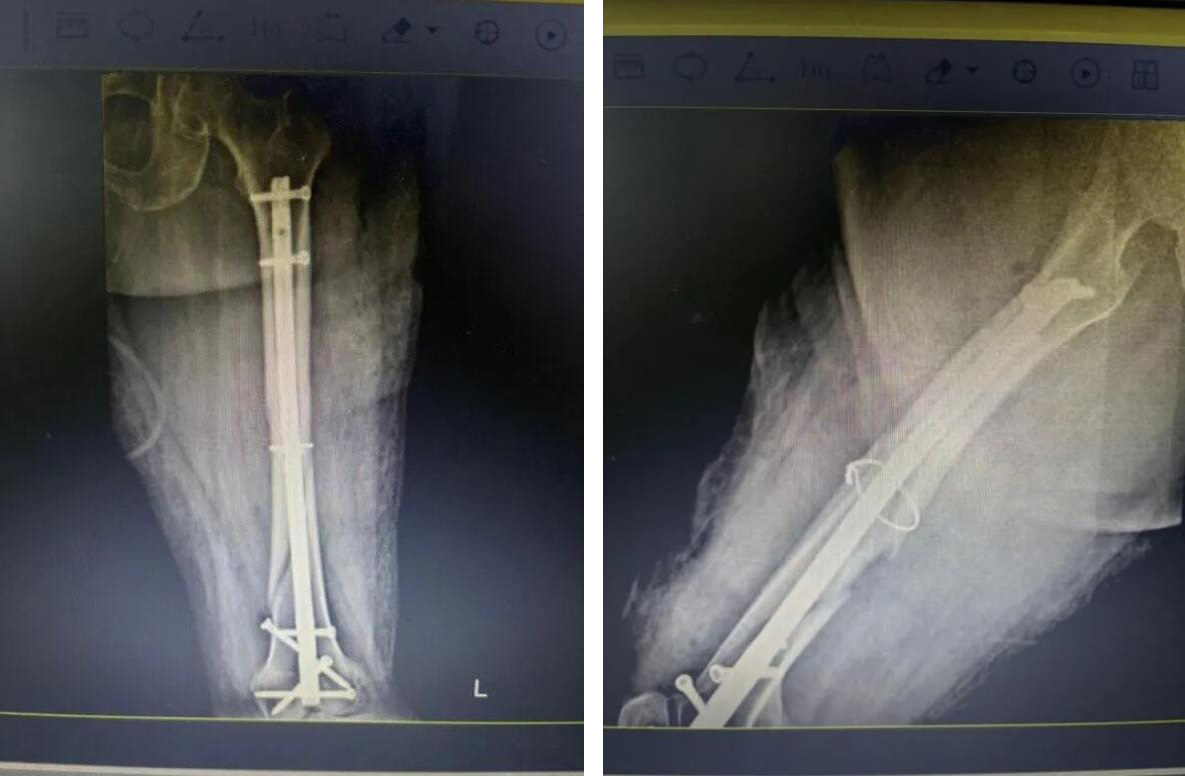

經(jīng)過(guò)充分準(zhǔn)備,醫(yī)療團(tuán)隊(duì)決定為俞奶奶實(shí)施 “閉合復(fù)位微創(chuàng)內(nèi)固定術(shù)”。

與傳統(tǒng)開(kāi)放手術(shù)不同,醫(yī)生不在骨折處做長(zhǎng)切口,而是通過(guò)幾個(gè)僅1-2厘米的“鑰匙孔”小切口,在C型臂X光機(jī)的精準(zhǔn)導(dǎo)航下,將骨折斷端巧妙地對(duì)合復(fù)位,然后植入髓內(nèi)釘進(jìn)行堅(jiān)固固定。

手術(shù)歷時(shí)約一小時(shí),過(guò)程非常順利。術(shù)中出血量極少,最大程度減少了對(duì)患者生理機(jī)能的干擾。